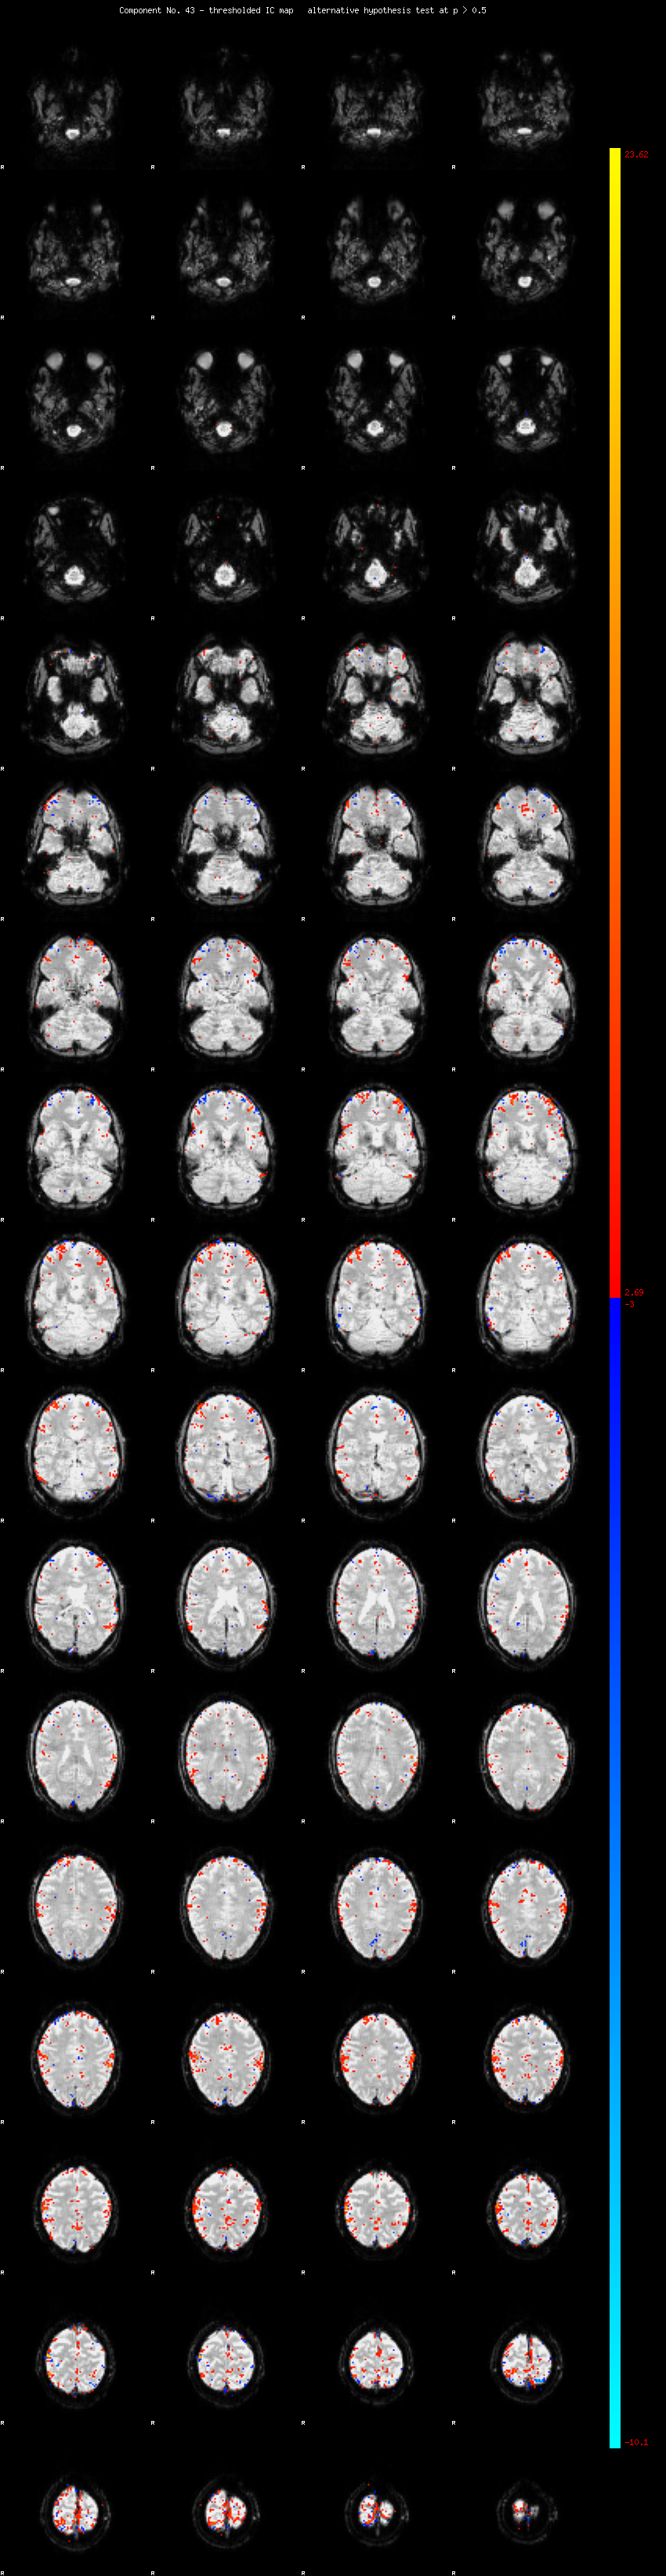

MELODIC Component 43

1.07 % of explained variance;     0.71 % of total variance

MMfit